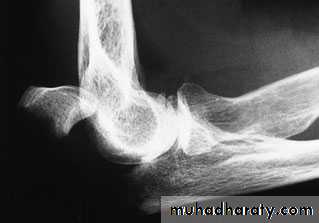

X-ray

3-Displaced transverse fractures can be held only by splinting the arm absolutely straight – but stiffness in that position would be disastrous. Operative treatment is therefore strongly recommended. The fracture is reduced and held by tension band wiring. Oblique fractures may need a lag screw, neutralised by a tension band system or plate.